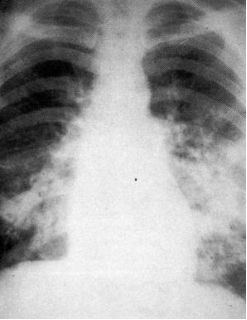

第一节:心源性肺水肿

典型患者有心脏病,突发气促,咳粉红色泡沫痰,典型影像学如下